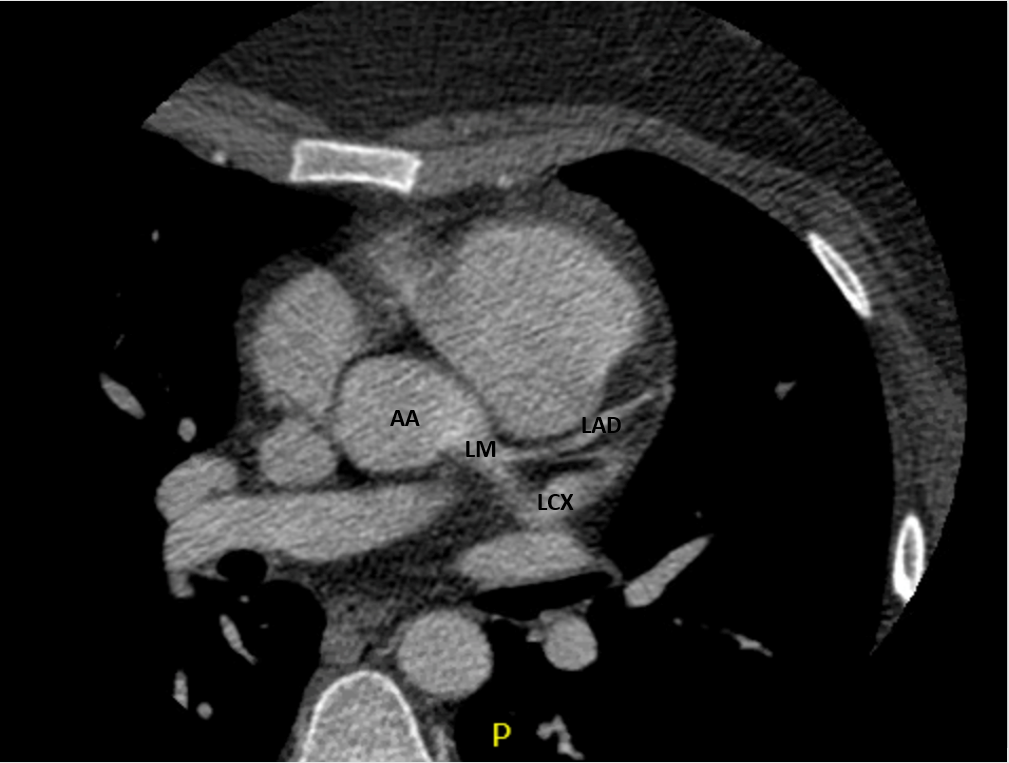

CT Heart

• Coronary artery fistula with features of macrofistulous communication of the distal left circumflex artery with the coronary sinus and presumed exophytic varix extending into the right atrium

• Circumflex measuring up to 9mm proximally and 26mm distally

Anatomy